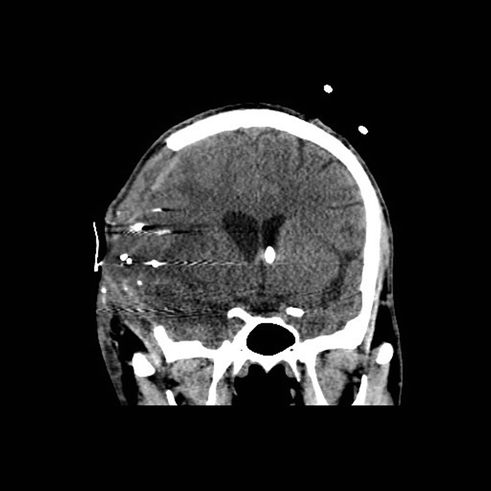

Fig. 19.2

Coronal head CT at the posterior border of the sphenoid sinus demonstrating a wide bifrontal craniectomy with extension to the middle cranial fossa floor

A 21-year-old male was involved in a T-bone collision while riding a motorcycle wearing a full face helmet. He was a GCS 3T on arrival to the hospital. His head injuries involved a left parieto-occipital contrecoup contusion and subtle bifrontal hypodensities and multiple orthopedic injuries. An EVD was placed and his intracranial pressures were managed medically for the first 5 days. Eventually the right parieto-occipital contusion and bifrontal hypodensities evolved causing 5 mm of left to right midline shift and medically refractory elevated ICPs > 20 mmHg. A wide bifrontal craniectomy was performed. He developed bilateral subdural hygromas 2 weeks after surgery that resolved spontaneously after 3 days of observation. He underwent a bifrontal cranioplasty 4 months after the craniectomy. He was discharged to neuro-rehab with a GCS 14. He has moderate cognitive changes and emotional lability consistent with his frontal lobe injury.